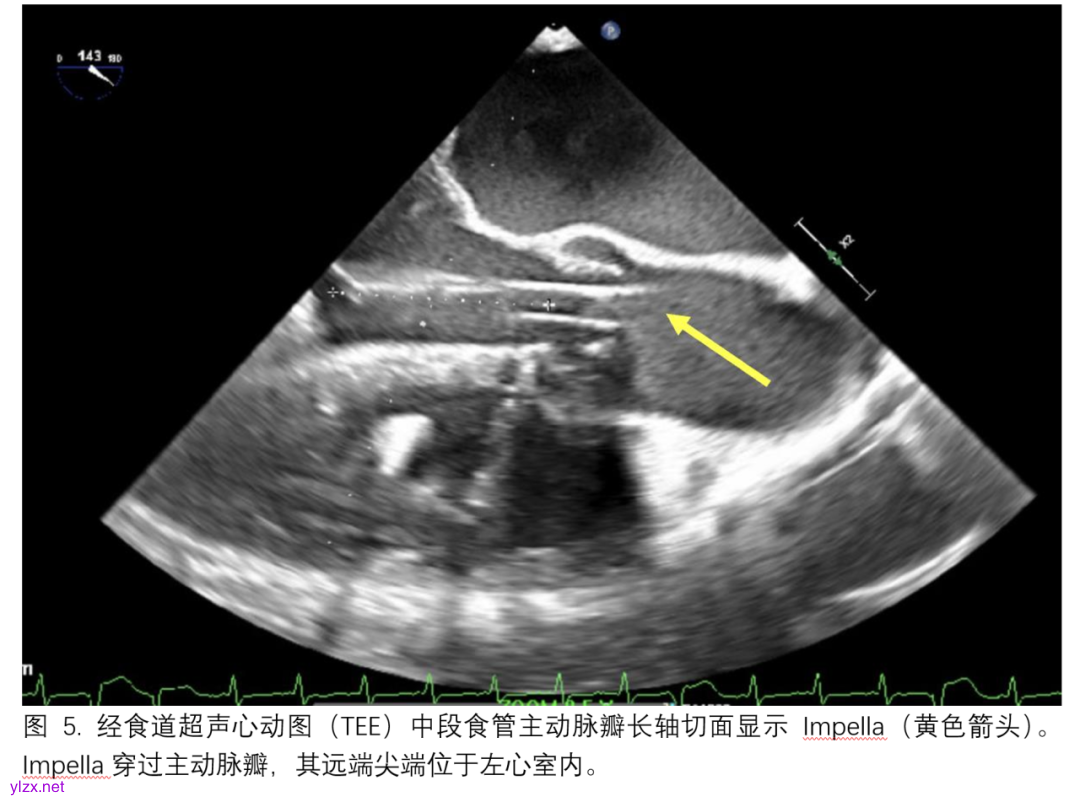

如果左心室减负不足,则需要放置左心室引流管(LV vent),并且与更高的ECMO撤机概率和降低死亡率相关。超声心动图可以作为放置和管理左心室引流管的有用指导工具,无论采用何种左心室引流策略。左心室引流管可以在经食道超声心动图(TEE)引导下直接放置在左心室心尖或左心房(通过肺静脉)。此外,左心室减负也可以通过房间隔造口术实现。房间隔造口术通常在TEE引导下进行,TEE有助于观察房间隔的“帐篷”效应,并且可以从正面提供三维图像引导,帮助介入医生进行精细的心内操作,避免心脏或血管损伤(图4)。主动脉内球囊反搏(IABP)是另一种常用于通过降低全身后负荷来解决左心室扩张的策略。当与ECMO联合使用时,IABP可以改善股动脉血流速度,并与单独使用ECMO相比提高总生存率。TEE引导已被用于指导IABP的适当放置。IABP导丝应被观察到位于左锁骨下动脉开口下方1-2厘米处,且应通过观察确认没有新的心脏损伤、主动脉夹层或与粥样硬化疾病发生干扰。最后,LV Impella(Abiomed)是一种小型化的左心室辅助装置,它提供从左心室到升主动脉的持续引流血流。它常与ECMO治疗联合使用,以提供左心室减负以及ECMO撤机后的过渡性机械循环支持,并且与单独使用ECMO相比,联合使用时与更高的生存率相关。TEE常用于指导Impella的放置,并应在主动脉瓣的室侧显示Impella尖端距离主动脉瓣环3.5-5.5厘米(具体取决于Impella型号),同时确认没有发生主动脉夹层、心包填塞或新的主动脉瓣或二尖瓣功能障碍,或卵圆孔未闭(图5)。